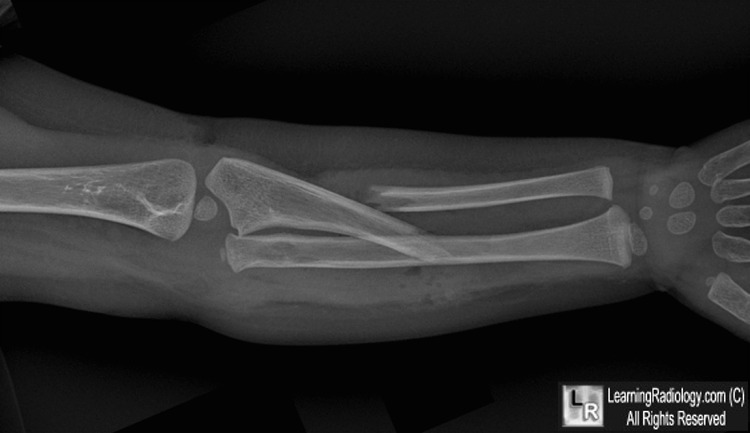

- Relatively uncommon fracture of the ulna with dislocation of the radial head

- Bado type 1 is most common: Fracture of the proximal or middle third of the ulna with anterior dislocation of the radial head

- Ulna fracture will usually show some positional deformity that produces shortening, such as angulation of the fracture, over-riding of the fragments or acute plastic deformation

- A line drawn longitudinally through the shaft of the radius should intersect the capitellum on all radiographs of the elbow

- The apex of the ulnar fracture almost always points in same direction as radial head dislocation